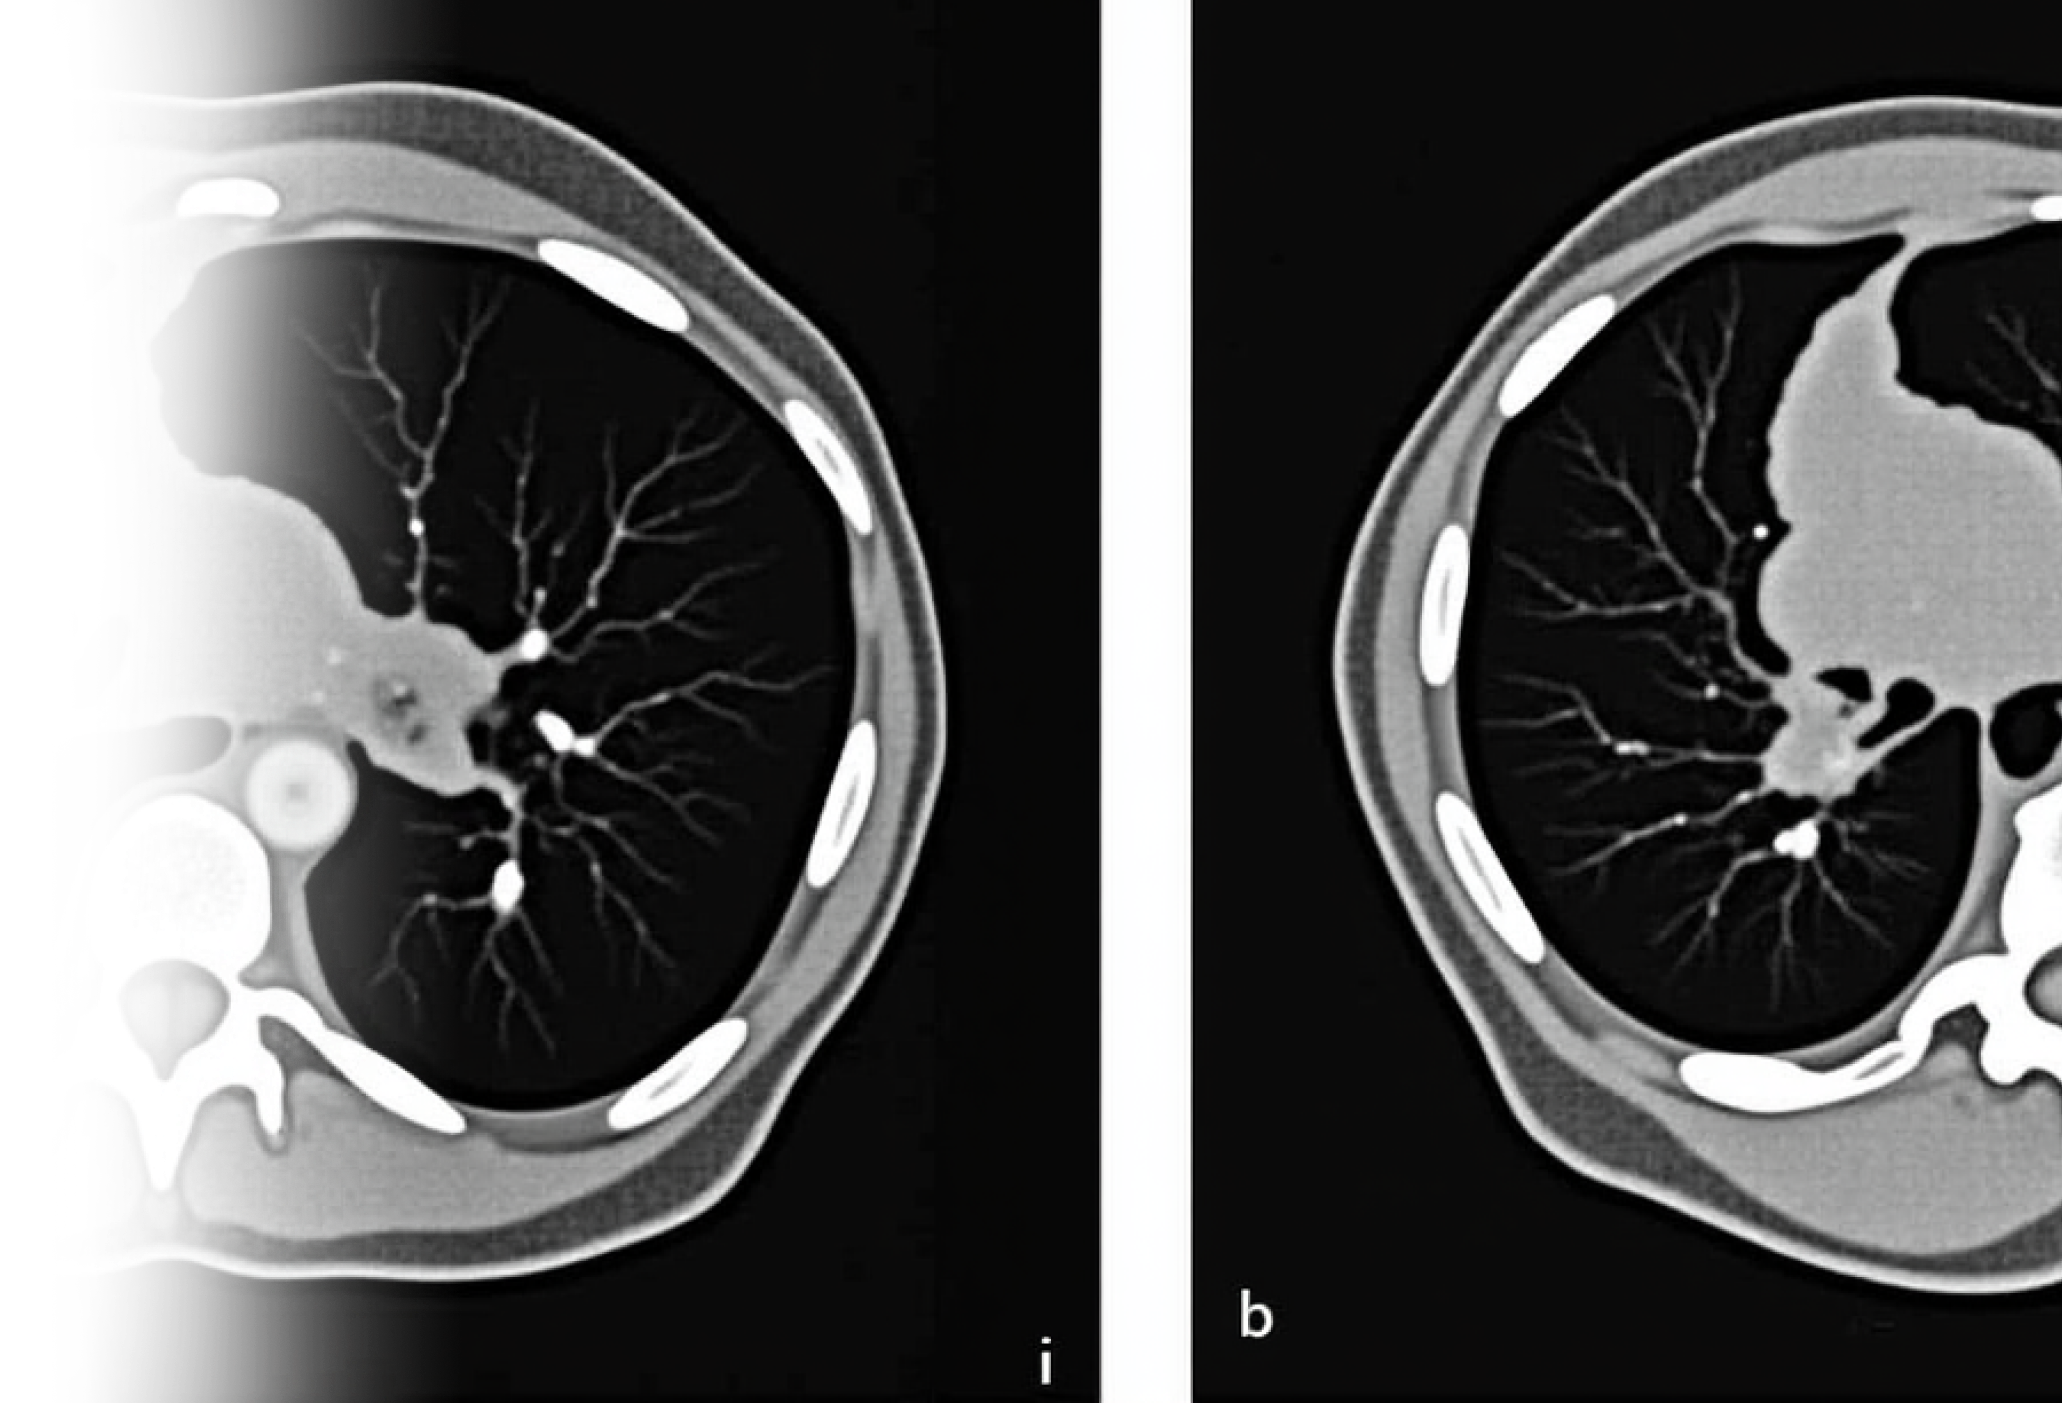

Компьютерная томография органов грудной клетки – важный метод исследования паренхимы легких, органов средостения, костного каркаса грудной клетки и мягких тканей.

Как проводится КТ органов грудной клетки?

Пациент ложится на стол сканера, который постепенно перемещается в аппарат. Во время сканирования следует лежать неподвижно, чтобы получаемые трехмерные изображения были четкими и неискаженными.